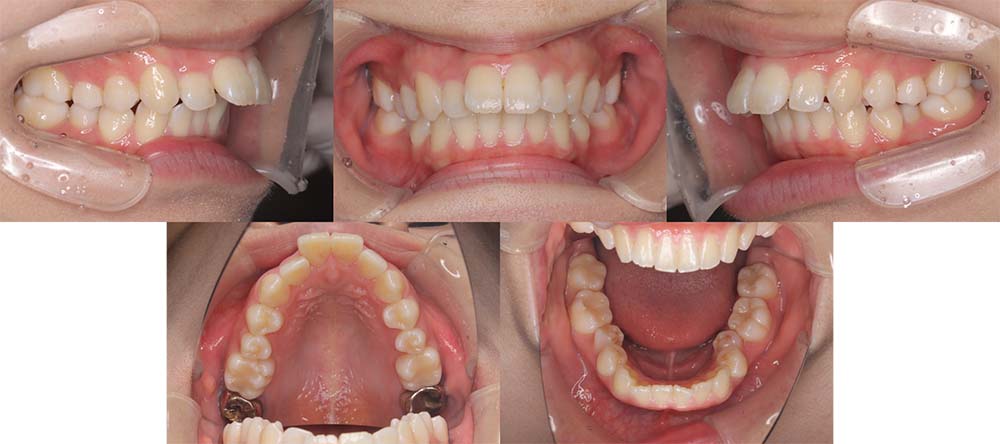

| 症例分類 | 上顎前突、叢生 |

| 診断名 | 上下叢生を伴う骨格性および歯性上顎前突 |

| 主訴 | 歯並びが悪いのが気になる、口元が気になる |

| 年齢 | 19歳5ヶ月 |

| 性別 | 女性 |

| 抜歯部位 | 上の左右第一小臼歯(2本) |

| 使用装置 | 上下裏側のワイヤー装置 |

| 治療期間 | 2年5ヶ月 |

| 保定装置 | 固定式保定装置、取り外し式保定装置(8時間) |

| 費用 |

[検査・診断料] ¥49,500 [基本施術料] ¥1,331,000 [調整料] ¥5,500/回 [抜歯] ¥5,500/本 [保定装置] ¥55,000(税込) 抜歯や虫歯治療は他院にて費用が別途かかります。(抜歯¥4,000〜10,000/本)

上顎前突で上の歯がかなり前にきているため、上顎両側第一小臼歯を抜去して治療を行いました。上の前歯をしっかりと舌側に移動しないといけないため、矯正用アンカースクリューを使用しました。また、下顎はわずかに歯の間の削合(ディスキング)を行い、初診時より歯が前方に出ないように治療を進めました。

口唇閉鎖不全もありましたが、上の前歯が舌側に移動することにより改善することができ、問題なく咬合させることができました。